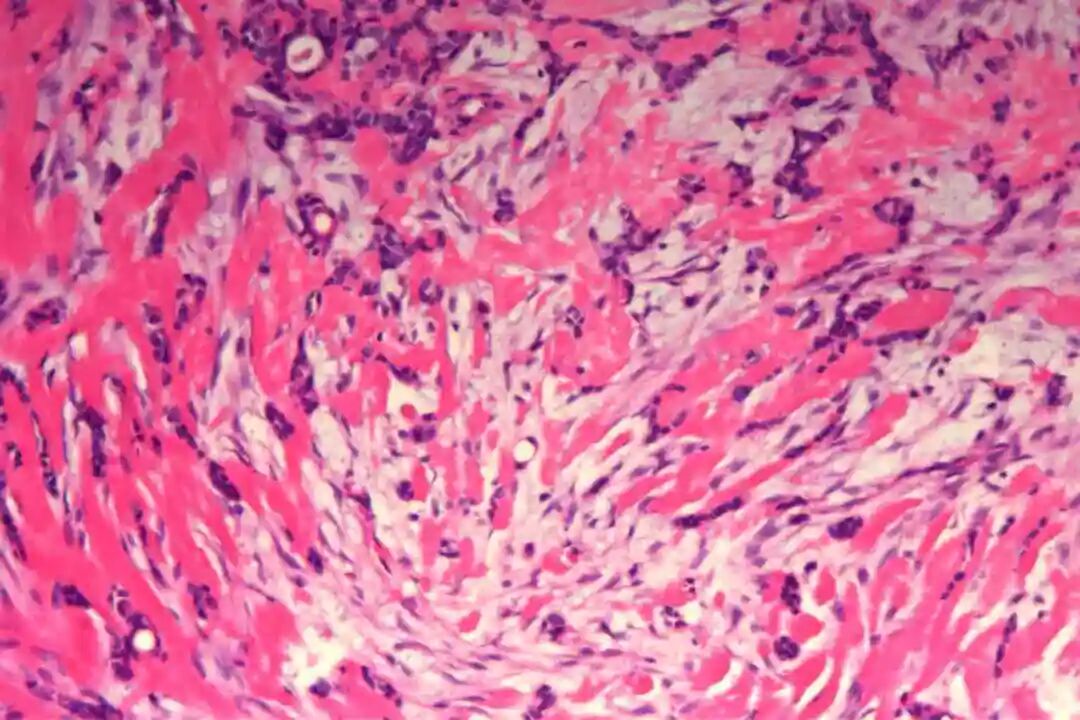

细胞形态:基底样肌上皮细胞体积较小,呈圆形或卵圆形,细胞核深染、染色质均匀,核仁不明显,胞质稀少、淡嗜酸性;腺上皮细胞体积略大,呈柱状或立方状,细胞核淡染、染色质疏松,核仁清晰,胞质丰富、嗜酸性。实性巢团内可见少量微小腔隙,腔隙内可含有少量嗜酸性或嗜碱性黏液样物质(PAS染色阳性),这是实体型与其他实性肿瘤的重要鉴别点;核分裂象少见,一般≤5个/10HPF,部分实体型区域可出现轻度至中度细胞异型性,但无明显恶性增殖活性表现,与高级别乳腺癌的细胞异型性有明显区别。

实体型区域与经典型区域无明显明确界限,相互穿插分布,实体型巢团可逐渐过渡为经典型的筛状或管状结构,两种区域的细胞成分相互延续,均可见腺上皮细胞与肌上皮细胞的混合存在,无明显细胞异型性差异(实体型区域异型性略高于经典型,但整体温和)。这种混合性形态是本病的重要镜下特点,也是与单纯实体型PACC、单纯经典型PACC的主要区别。